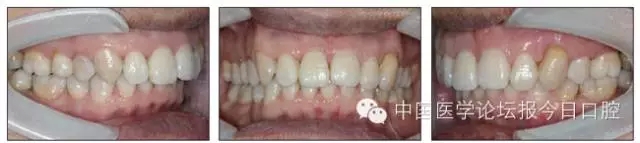

保持階段

18.webp.jpg

19.webp.jpg

圖12 保持半年后口內(nèi)像